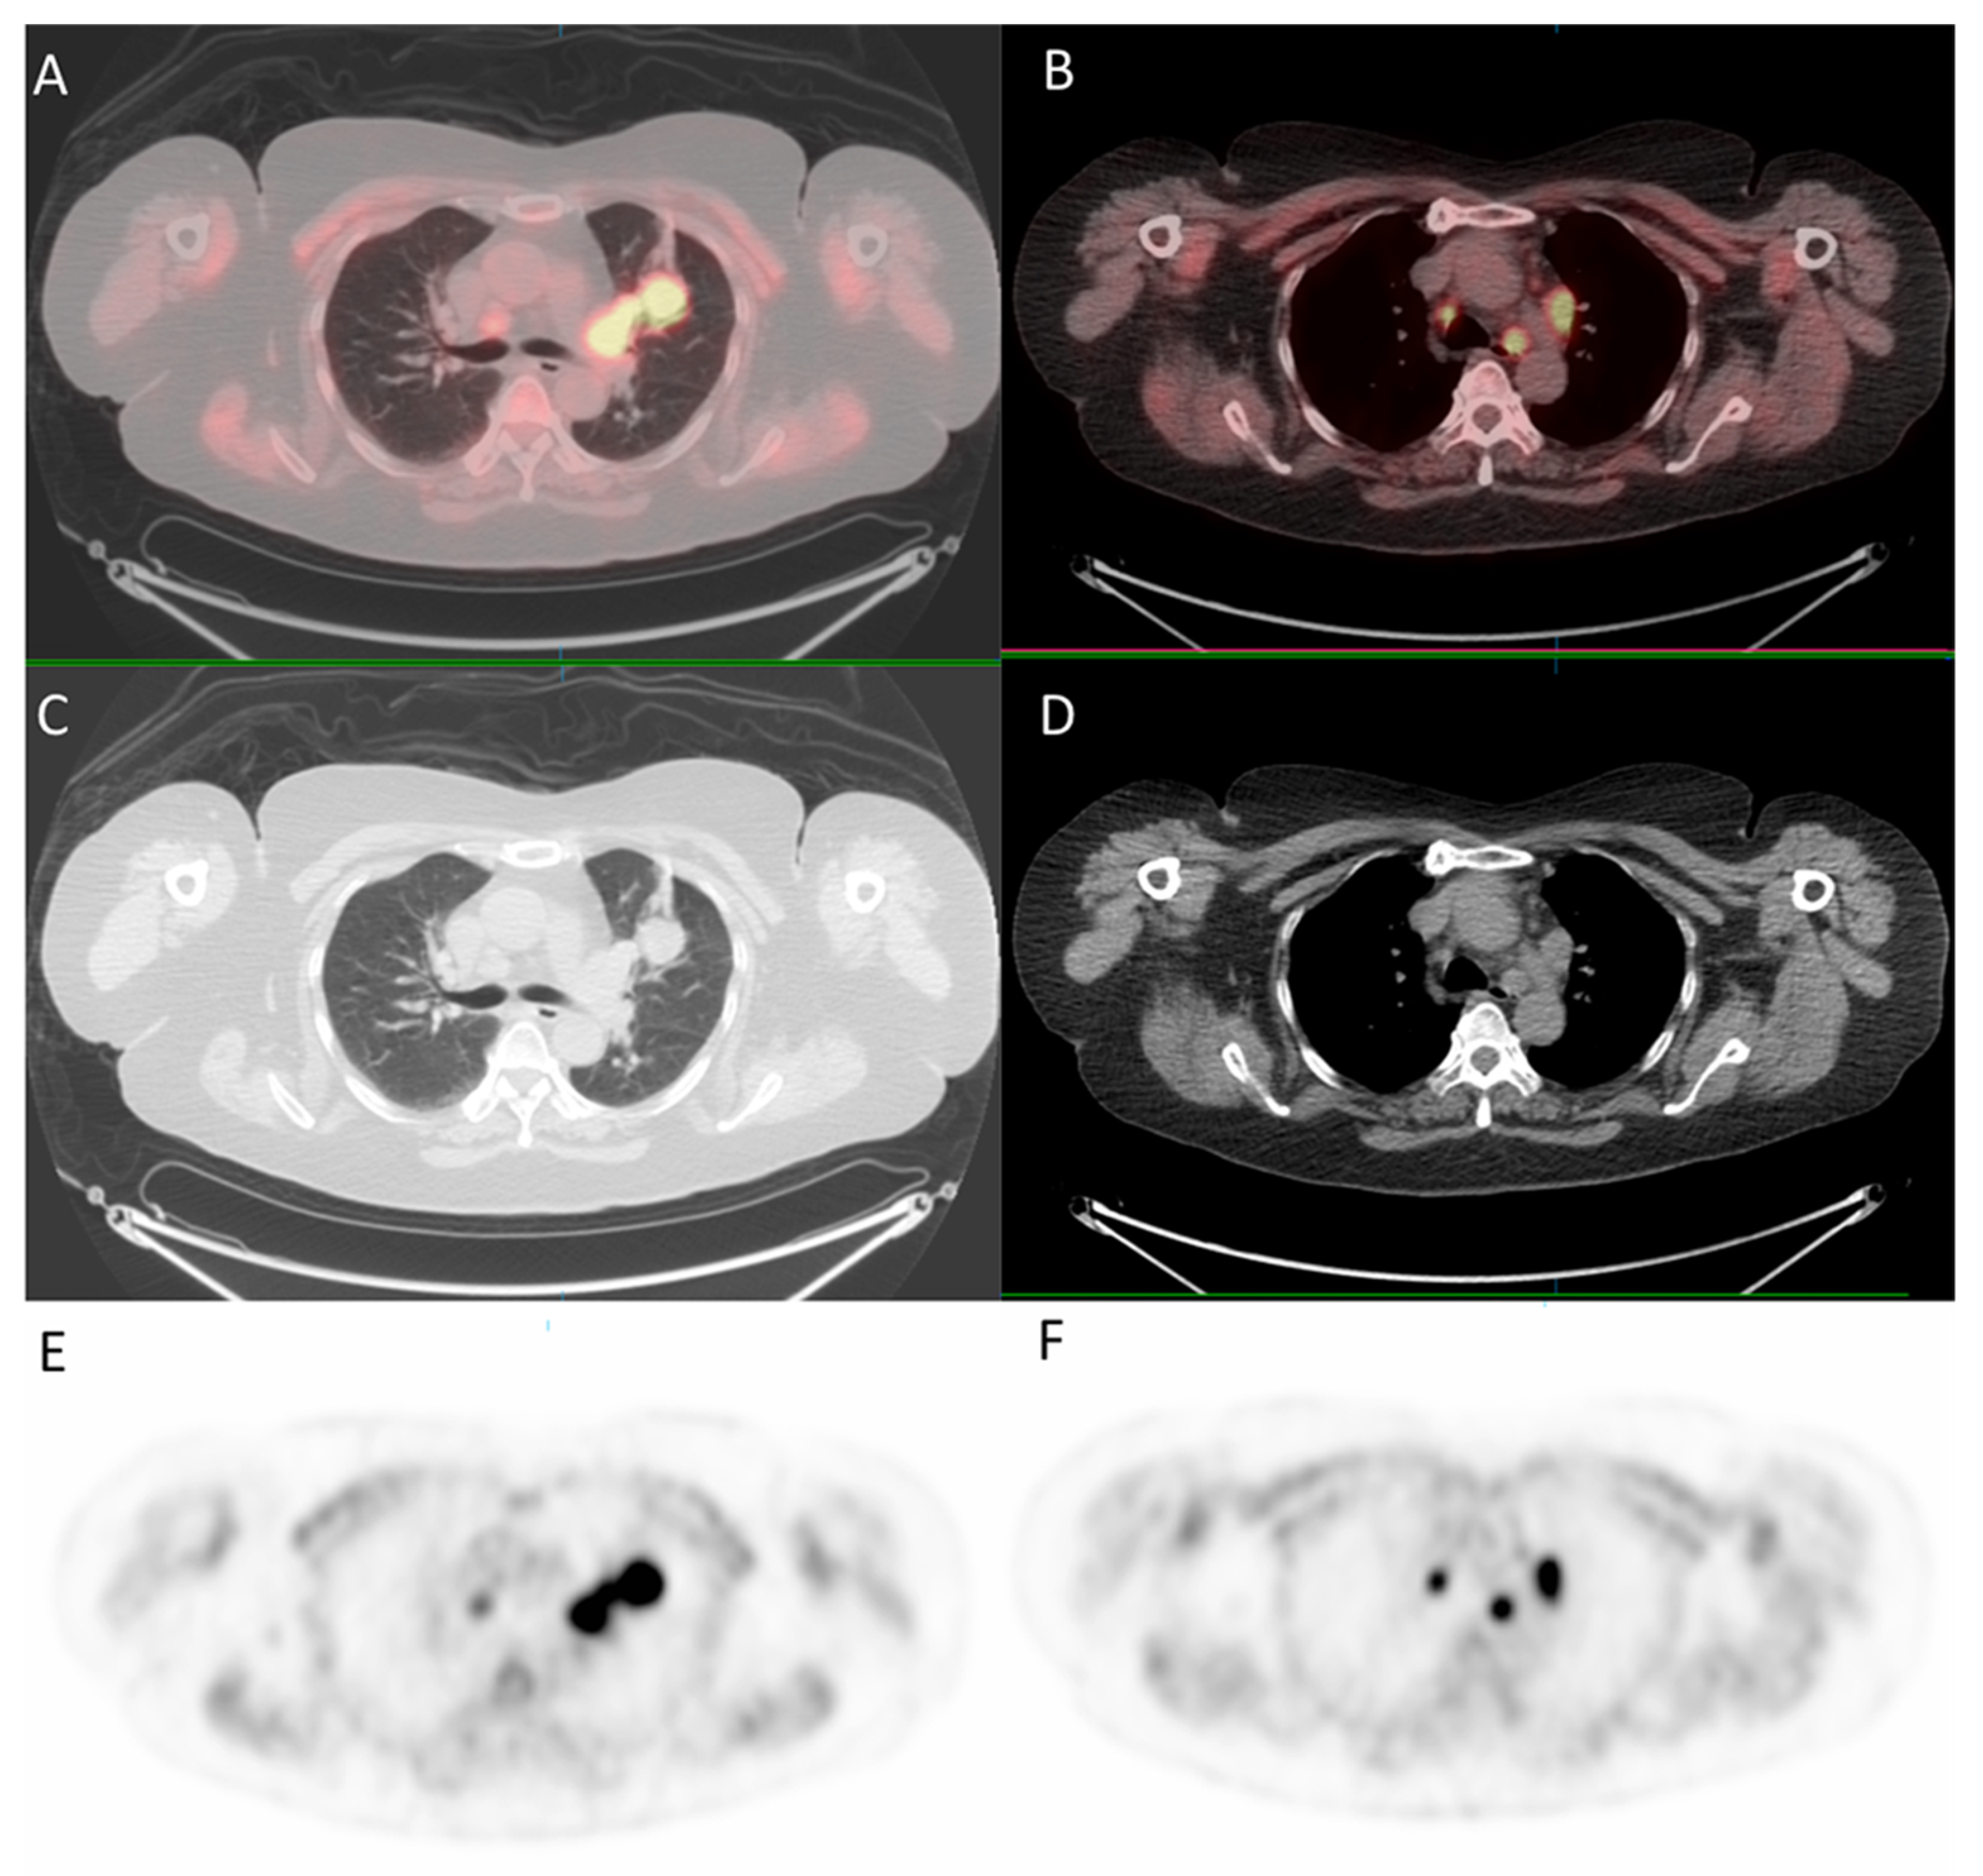

Since the patient had a family history of lung cancer, whole-body positron emission tomography/computed tomography (PET/CT) was suggested; the results showed focal uptake in the left eye with a standardized uptake value (SUV) of 10.8, left upper lung (SUV: 11.5), mediastinum (SUV: 14.8), liver (SUV: 9.6), and bone (SUV: 10) (Figure 5 and Figure 6).

Figure 5.

18F-fludeoxyglucose positron emission tomography/computed tomography (18F-FDG PET/CT) for whole-body evaluation. (A,B) axial fused PET/CT showing focal uptake of the lung and mediastinum, respectively; (C,D) axial CT; (E,F) PET.

In the last decade, conventional imaging modalities, such as plain radiography, ultrasound, CT, and magnetic resonance imaging, have been widely used to provide clear structural images of the tumor [16]. PET, which uses short-lived radioisotopes, such as fluorine-18 to label glucose, can detect malignancy and be used for staging, restaging, or monitoring treatment responses [17]. PET combined with CT provides simultaneously high sensitivity of tracer distribution and high precision of localization, facilitating the detection of tumor sites in patients with choroid metastasis. In the present case, PET/CT scan was utilized early for detection of tumor sites, and it highlighted multiple uptakes in the left eye, left upper lung, mediastinum, liver, and bone. In addition to providing useful clues to the possible primary tumor sites, it was fast and efficient.